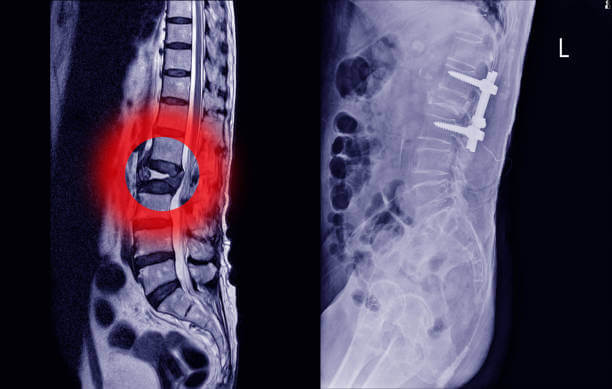

허리디스크(추간판 탈출증)은 척추뼈와 척추뼈 사이의 구조물인 디스크가 탈출된 상태입니다. 일반적으로 허리디스크라고 부르지만 디스크는 구조의 명칭일 뿐, 허리디스크에 해당하는 정확한 질환명은 '허리추간판 탈출증'입니다.

디스크 또는 추간판은 탄성이 뛰어나 외부로부터의 물리적 충격을 완화하고 단단한 뼈 사이의 직접적인 충돌을 방지합니다. 외부의 큰 충격이나 잘못된 자세로 인해 이 디스크가 돌출되면 염증을 일으키고 신경을 압박해 허리 통증, 방사선 통증 등의 통증을 유발합니다.

말기 단계

추간판 탈출증 상태에서는 수핵의 일부가 섬유륜을 찢고 추간판 조직과 분리됩니다. 심한 요통과 일상생활이 불가능할 정도로 움직임이 심하게 제한됩니다. 요통이 심해지면 하반신 마비로 이어질 수 있어 빠른 치료를 해야합니다.